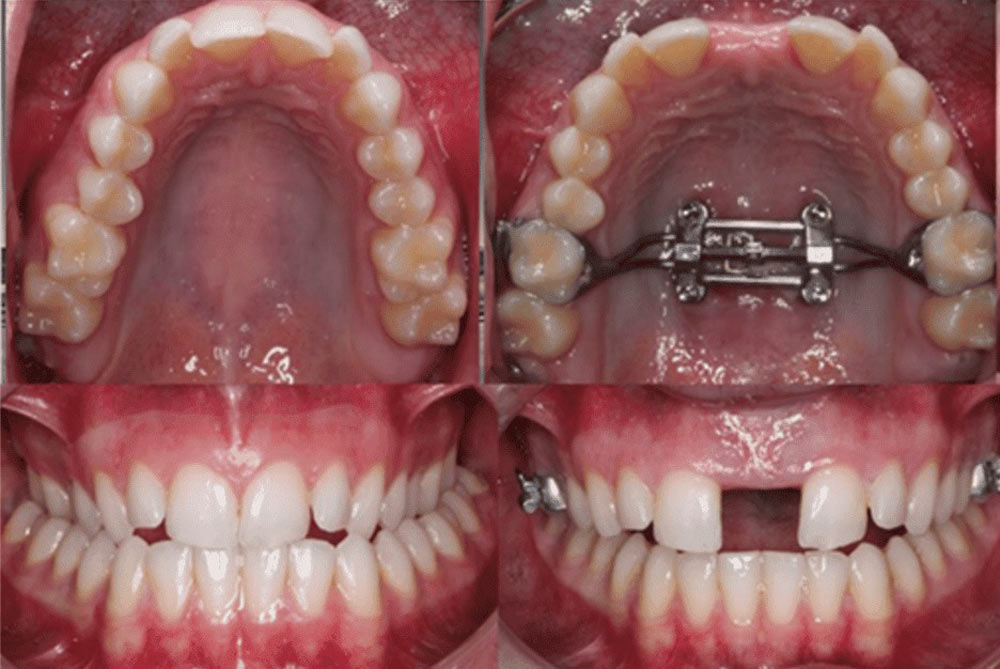

2. وسیع کننده سریع کام (RPE) : این وسیله بر روی دندان های آسیای فک بالا ثابت می شود و دارای پیچ کوچکی در مرکز است. این وسیله مجهز به یک کلید کوچک است که برای اعمال فشار ملایم به دندان ها به کار می رود؛ به طوری که در نهایت، فک به تدریج پهن تر می گردد. در واقع، این وسیله می تواند به طور روزانه تقریبا 0.5 میلی متر، به پهنای فک بیافزاید. به طور کلی، دستیابی به نتایج مطلوب نیز معمولا در طول ۳ تا ۶ ماه حاصل خواهد شد.

3. نصب پالاتال اکسپندر با کمک مداخلات جراحی (SARPE): این نوع از اکسپندرها را برای رفع اختلالات دندانی بزرگسالان و برای بیمارانی که مشکلات دندانی شدیدتری دارند، طراحی کرده اند. جراح متخصص دستگاه را در خط میانی فک نصب می کند. این اکسپندر، درست مانند وسیع کننده سریع کام (RPE)، فشار ملایمی را به دندان های عقبی فک بالا وارد می کند. در نهایت نیز عرض مورد نظر در فک ایجاد خواهد شد.

4. وسیع کننده کام ایمپلنت شده: این نوع از اکسپندرها بیشتر برای درمان اختلالات دندانی نوجوانان و بزرگسالان قابل استفاده می باشد. این وسیله به استخوان های مینی ایمپلنت های دندانی، فشار وارد می کند. در واقع، هیچگونه فشاری به صورت مستقیم به خود دندان ها وارد نخواهد شد. در نتیجه، این روش باعث اثرگذاری بیشتر و کاهش فشار روی دندان ها خواهد شد.